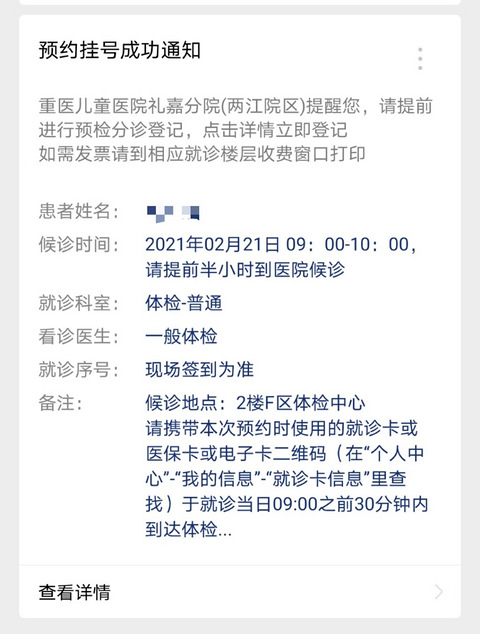

儿童医院体检中心一小时游

经常发八卦贴的我,来育儿板块发帖子了。萱萱妹的身高,一直是我最担心的,有半年没有检查身高了,听说儿童医院有体检中心,体检中心在儿童医院礼嘉分院二楼F区,都想挂号去体验下。我提前三天挂了体检中心的号。号不翘,随时都可以抢到。约起,约起,约起!

Miss猪小妹 2021-02-21 11:1177814 310